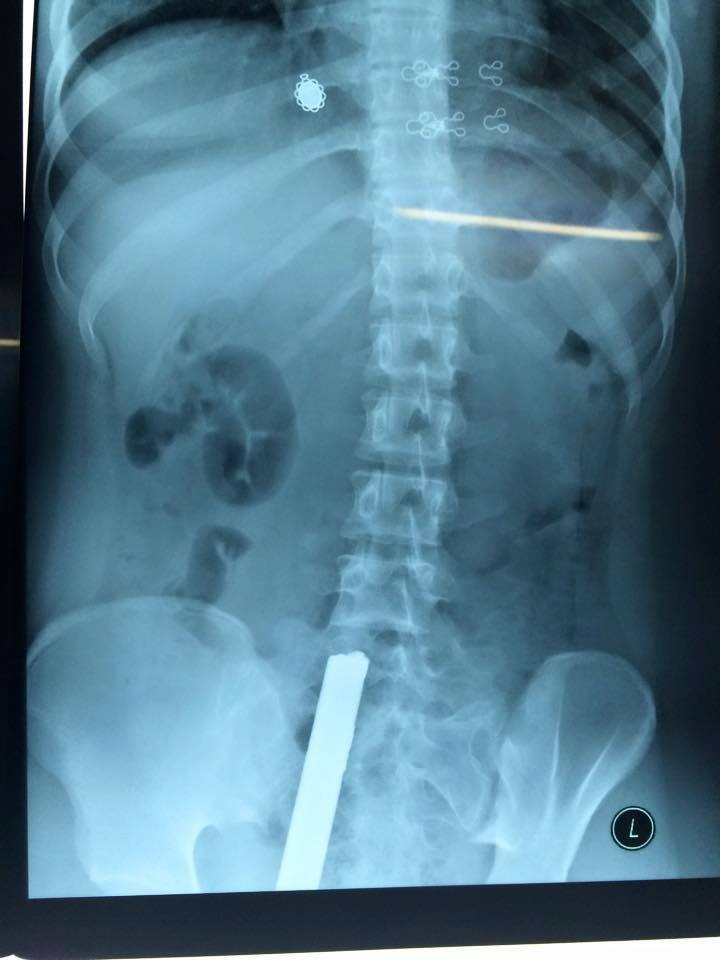

Ngay sau khi nhập viện, các bác sĩ nhanh chóng đưa bệnh nhân đi chụp X-quang.

| Thanh sắt đâm từ phía sau, phần dưới mông lên tận thắt lưng của cô gái.

Kết quả cho thấy thanh sắt đâm từ phía sau, phần dưới mông lên tận thắt lưng của cô gái. Bệnh nhân ngay lập tức được chuyển đến phòng phẫu thuật. Tối cùng ngày, sức khỏe bệnh nhân đã ổn định hơn và tiếp tục được theo dõi.

Theo các bác sĩ tại Bệnh viện Hữu nghị Việt Đức, may mắn thanh sắt chỉ đâm vào phần mềm, không ảnh hưởng đến xương và thần kinh.